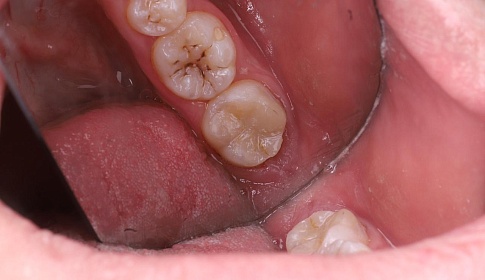

Средний

Средний кариес развивается, если не лечить заболевание на ранних стадиях. На этом этапе происходит достаточно быстрое разрушение зуба, потому что микроорганизмы достигают дентина. Зуб становится чувствительным к различным раздражителям, однако неприятные ощущения быстро проходят, стоит только раздражитель убрать. Это стадия, когда еще можно пройти лечение без осложнений. При лечении врач удалит налет, сделает анестезию, тщательно очистит и обработает пораженный участок, нанесет специальный адгезивный материал, выполнить пломбирование.